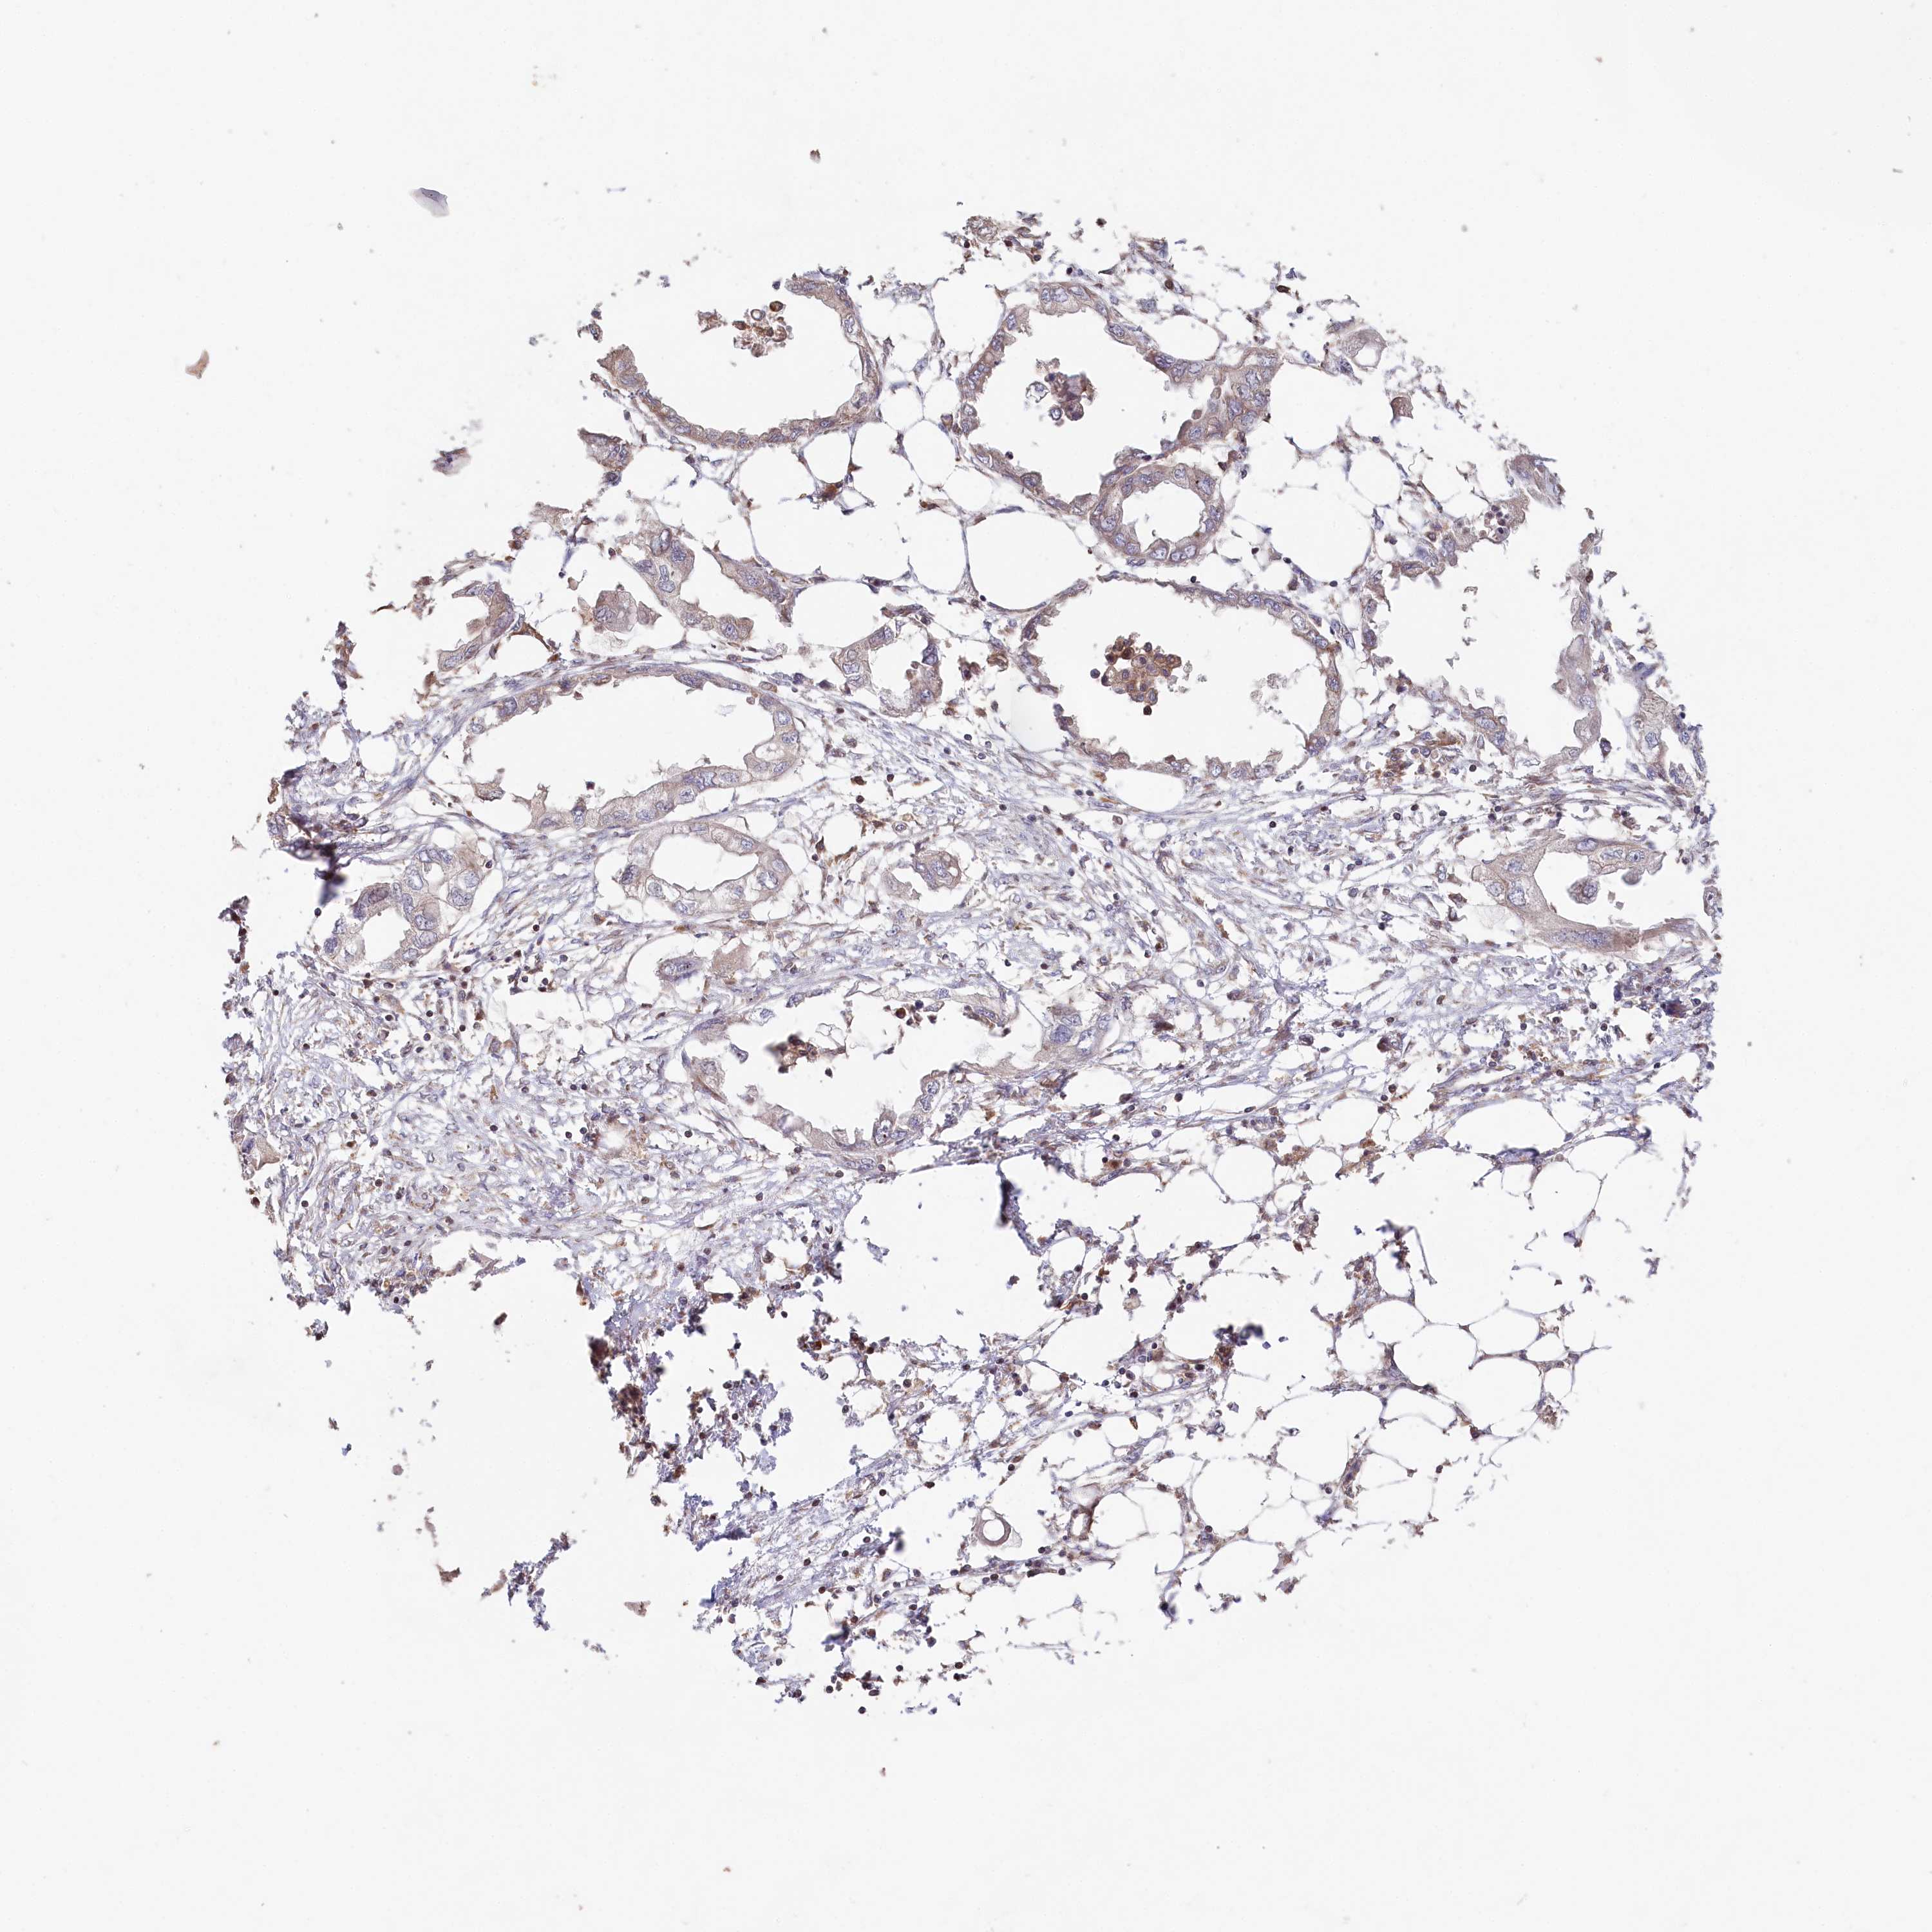

ENDOMETRIAL CANCER - Protein expressioni

A mouse-over function shows sample information and annotation data. Click on an image to view it in a full screen mode. Samples can be filtered based on level of antibody staining by selecting one or several of the following categories: high, medium, low and not detected. The assay and annotation is described here.

Note that samples used for immunohistochemistry by the Human Protein Atlas do not correspond to samples in the TCGA dataset.

Antibody stainingi

Antibody staining in the annotated cell types in the current human tissue is reported as not detected, low, medium, or high, based on conventional immunohistochemistry profiling in selected tissues. This score is based on the combination of the staining intensity and fraction of stained cells.

Each image is clickable and will lead to virtual microscopy that enables deeper exploration of all samples and also displays staining intensity scores, fraction scores and subcellular localization as well as patient and tissue information for each sample.

Antibody HPA038547

Antibody HPA038548

Staining

High

Medium

Low

Not detected

Intensity

Strong

Moderate

Weak

Negative

Quantity

>75%

75%-25%

<25%

None

Location

Nuclear

Cytoplasmic/membranous

Cytoplasmic/membranous,nuclear